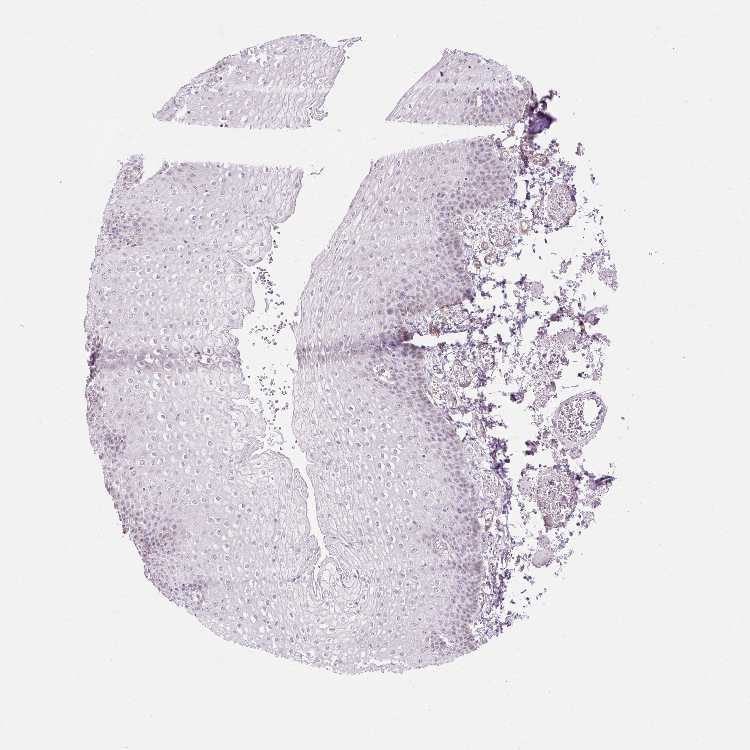

ESOPHAGUS - Antibody stainingi

Antibody staining in the annotated cell types in the current human tissue is reported as not detected, low, medium, or high, based on conventional immunohistochemistry profiling in selected tissues. This score is based on the combination of the staining intensity and fraction of stained cells.

Each image is clickable and will lead to virtual microscopy that enables deeper exploration of all samples and also displays staining intensity scores, fraction scores and subcellular localization as well as patient and tissue information for each sample.

Antibody HPA051859Antibody HPA054738

Squamous epithelial cells LowNot detected